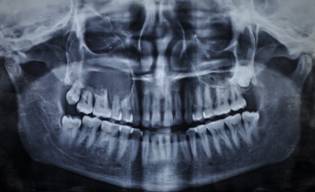

PRE OP OPG AND P A WATER'S VIEW SHOWS DISEASE

OPG SHOWS RECONSTRUCTION OF MAXILLA WITH OSTEOMYOCUTANEOUS ILLIAC BONE GRAFT AND IMPLANTS